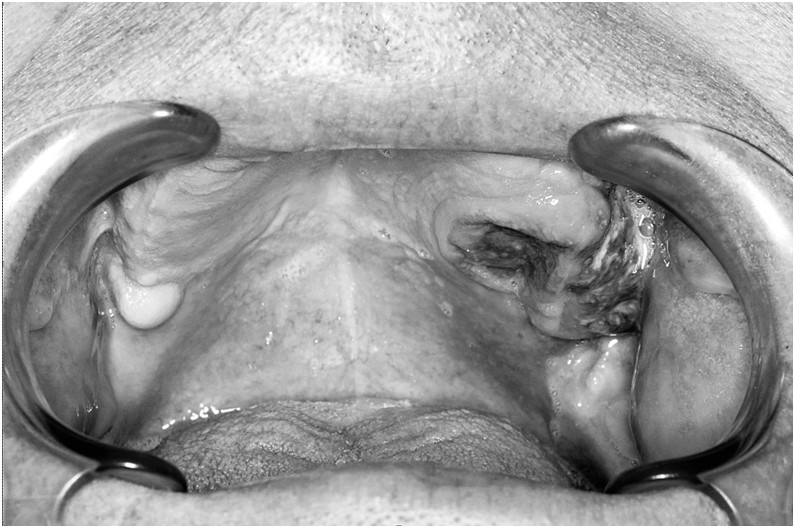

Pacjentka podaje bóle i wygórowanie w okolicy podżuchwowej po stronie prawej zwykle w czasie posiłków. Wynik pantomogramu przedstawiono poniżej. Co jest przyczyną podawanych objawów?